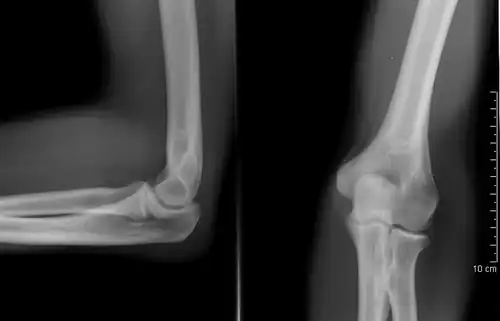

Right: AP X ray of a dislocated right elbow

There are three bones at the elbow joint, and any combination of these bones may be involved in a fracture of the elbow. Patients who are able to fully extend their arm at the elbow are unlikely to have a fracture (98% certainty) and an X-ray is not required as long as an olecranon fracture is ruled out.[27] Acute fractures may not be easily visible on X-ray.[28]

Dislocation

Elbow dislocations constitute 10% to 25% of all injuries to the elbow. The elbow is one of the most commonly dislocated joints in the body, with an average annual incidence of acute dislocation of 6 per 100,000 persons.[30] Among injuries to the upper extremity, dislocation of the elbow is second only to a dislocated shoulder. A full dislocation of the elbow will require expert medical attention to re-align, and recovery can take approximately 6 weeks.